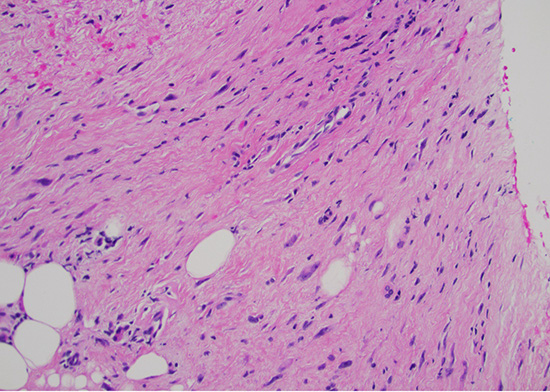

Histological examination demonstrated an infiltrative cellular proliferation of spindle and pleomorphic cells, with mild to moderate cytologic atypia and no necrosis (Fig 1). Mitotic figures were not seen.

Figure 1: H&E stain at 200x magnification displaying mild to moderate cytologic atypia without necrosis or mitoses.